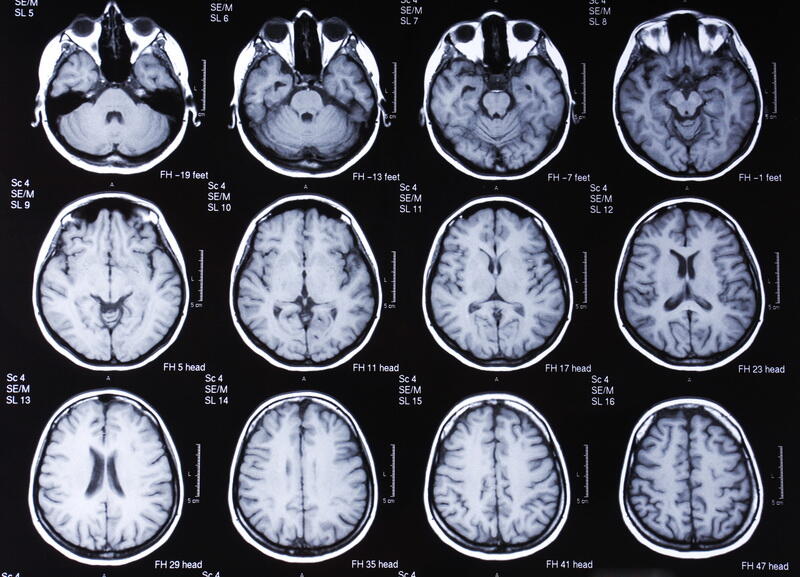

Damar demensiyasına diaqnoz qoymaq üçün həkim gündəlik fəaliyyətlərlə bağlı problemlər barədə soruşa, yaddaş və ya düşüncə testləri keçirə və demensiya əlamətlərinin olub-olmadığını öyrənmək üçün həmin şəxsi yaxşı tanıyan biri ilə danışa bilər. Xəstəlik tarixi, həyat tərzi məlumatları və beyin görüntüləmələri damat demensiyası simptomlarının səbəbi olub-olmadığını müəyyən etməyə kömək etmək üçün istifadə edilir.